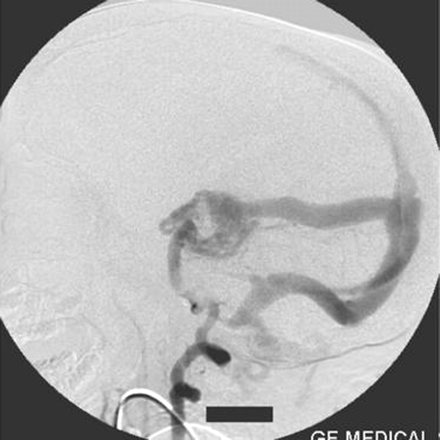

On the right external carotid artery angiogram, the carotid-basilar anastomotic vessel was seen to arise from the external carotid artery at the second cervical vertebral body (C2) level. The vessel coursed dorsally and joined the vertebral artery in the suboccipital space (Figs 6, 7). Contrast medium was seen to opacify the fistulous site and was draining via the left transverse sinus.

Right external carotid artery injection lateral view angiogram shows the proatlantal artery.

Right external artery injection anteroposterior view angiogram shows the opacification of the proatlantal artery of the right side.